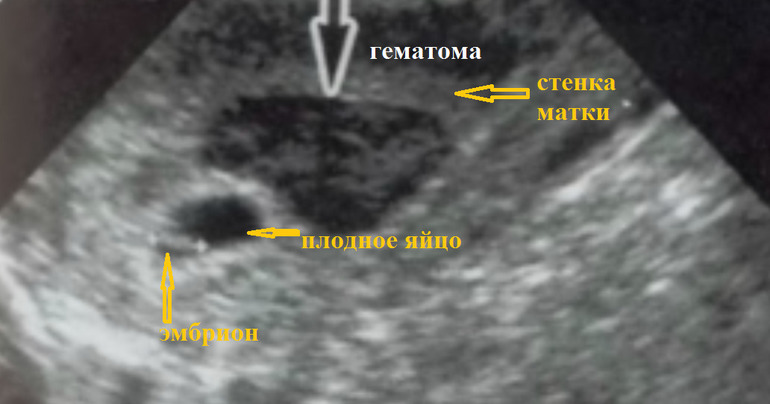

вот как вылдялят гематомы